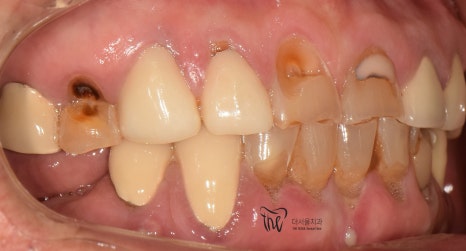

정면에서 봤을 땐, 비심미적인 모습을 보여주며

곳곳에 치경부파절증의 증세들이 드러나고

있습니다. 따라서 ,식사를 하실 때 마다

지끈거리는 통증 및 이가 시린 느낌을 지속적으로

받아오셨다 말씀을 하셨었죠.